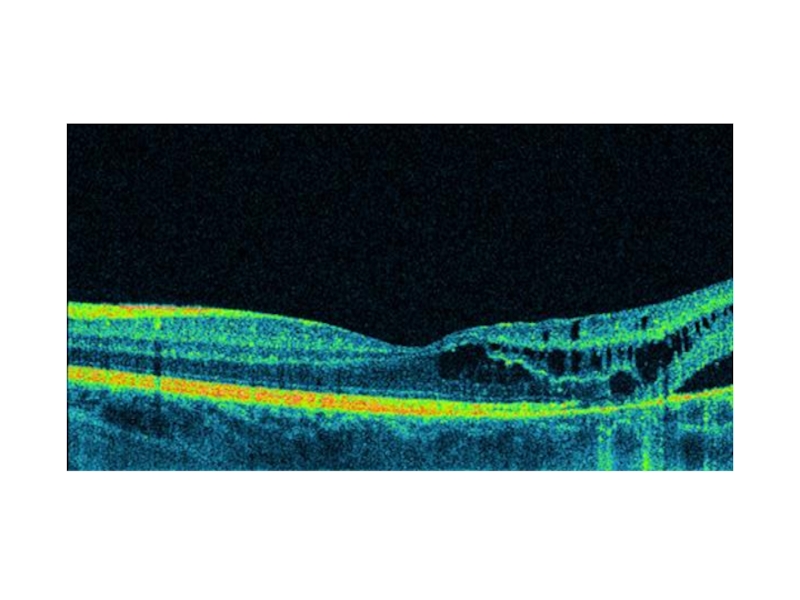

Офтальмологическая картина складывается из трех основных признаков: фовеолярного ретиношизиса, периферического ретиношизиса и изменения стекловидного тела.

Слайд 10Фовеолярный ретиношизис

Характеризуется наличием нежных кистовидных пространств в виде радиальных полос

симтом «спиц в колесе» или «депигментированная звезда»: небольшие нежные складки

внутренней пограничной мембраны, сходящиеся радиально к центру фовеа

Слайд 13По мере прогрессирования процесса ( увеличение по высоте фовеолярного ретиношизиса)

клиническая офтальмологическая картина меняется: вместо радиарной исчерченности появляется «валикообразное» циркулярное

образование с втянутым центром в области фовеа, имеющее вид пончика за счет проминенции внутренних слоев сетчатки вокруг фовеа.